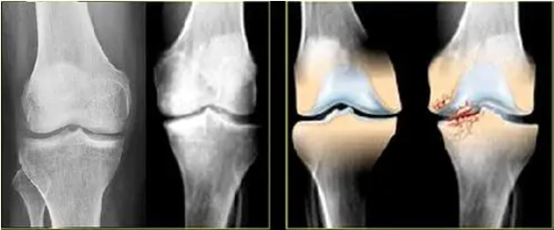

膝盖疼痛,上下楼梯都困难!关节僵硬、疼痛,膝关节半月板损伤、积液等关节问题,后悔没早点用这个方法,好几万块都白花了!

我是来自四川的患者儿子,我母亲今年52岁,去医院检查,医生说右膝关节位置半月板损伤、滑膜炎积液吃过不少止疼药,抽过积液、注射过玻璃酸钠,只能短暂缓解疼痛,总是反复,朋友介绍也带着我母亲做针灸、按摩、小针刀等,但都是徒劳,目前我妈已经严重的走不了路,抬不起腿,关节积液肿胀僵硬、弯腿还能听到咔哧的声音,天天备受疼痛折磨,面对痛苦的煎熬,妈妈整日面容憔悴,我也是整日愁眉不展。

我只是简单的分享一下自己带着母亲的求医经历,我母亲的切身体会是,调理指导老师的中药是一人一方,辨证施治,疗效可观,对大多数关节僵硬、疼痛、膝关节半月板损伤、膝关节骨刺、滑膜炎积液等关节问题疼痛,效果还是比较显著的,东西实实在在的,比那些机械量产的膏药、理疗、手术靠谱安全太多了。